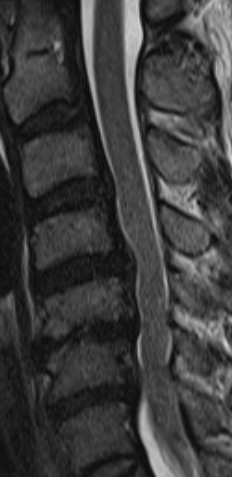

腰部打撲で新鮮なヘルニアと診断された画像

歩行中、乗用車と接触し転倒し受傷。

L4/5、5/S1椎間板の後方膨隆がみられます。

主治医は、L4/5のヘルニアにつき、水分含有量などから新鮮なヘルニア(外傷性)と判断しました。

同上 L4/5の横断画像

ほぼ正中のヘルニアの膨隆により、神経根を圧排している所見が得られています。

左下肢痛、左足底(S1神経根の支配領域)の痛覚・触覚の低下を訴え、

左腓腹筋の筋力低下、

アキレス腱反射の低下

ラセーグ、SLRテスト、50度

などの神経学的異常所見が得られ、12級13号の認定を受けました。